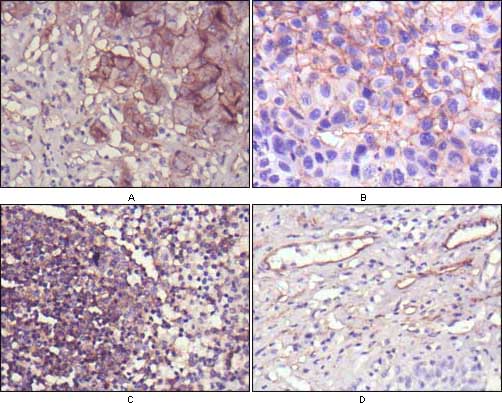

ERBB3, v-erb-b2 erythroblastic leukemia viral oncogene homolog 3 (avian). It is a member of the epidermal growth factor receptor (EGFR) family of receptor tyrosine kinases. This membrane-bound protein has a neuregulin binding domain but not an active kinase domain. It therefore can bind this ligand but not convey the signal into the cell through protein phosphorylation. However, it does form heterodimers with other EGF receptor family members which do have kinase activity. Heterodimerization leads to the activation of pathways which lead to cell proliferation or differentiation. Amplification of this gene and/or overexpression of its protein have been reported in numerous cancers, including prostate, bladder, and breast tumors. Alternate transcriptional splice variants encoding different isoforms have been characterized. One isoform lacks the intermembrane region and is secreted outside the cell. This form acts to modulate the activity of the membrane-bound form. Additional splice variants have also been reported, but they have not been thoroughly characterized. |

| ICC | 1/200 - 1/1000 |